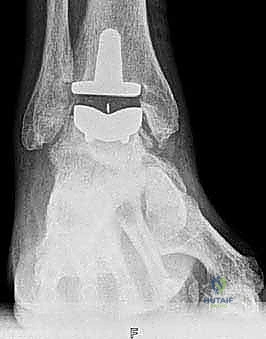

يتكون مفصل الكاحل الصناعي الحديث عادة من ثلاثة أجزاء:

* قطعة معدنية علوية: تُثبت في عظمة الظنبوب (الساق).

* قطعة معدنية سفلية: تُثبت في عظمة الكاحل.

* قطعة بلاستيكية (بولي إيثيلين عالي الكثافة): توضع بين القطعتين المعدنيتين لتنزلق بسلاسة وتمتص الصدمات، محاكيةً وظيفة الغضروف الطبيعي.

يتم تثبيت هذه الأجزاء بإحكام (إما عن طريق الضغط المباشر لتشجيع نمو العظم حولها، أو باستخدام أسمنت طبي خاص).